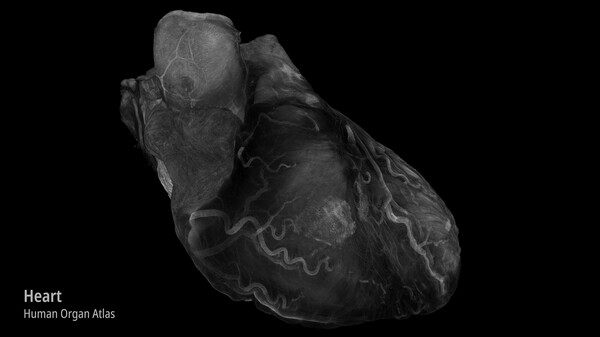

Step into massive 3D images made up of billions of voxels and explore the internal structures of real objects, from animals and human organs to complex materials and devices.